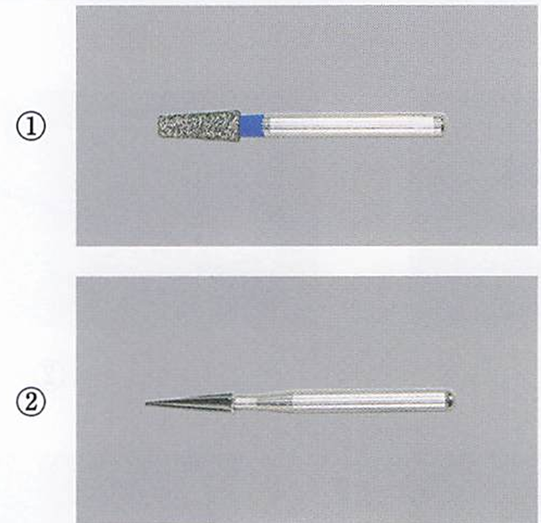

午前-96

50歳の男性。上顎左側第一大臼歯の自発痛を主訴として来院した。 3か月煎から強い冷水痛があったがそのままにしていたところ、昨夜食事中に修復物が脱離して、自発痛が生じたという。冷水を口に含むと一時的に疼痛が緩和するという。打診痛を認めた。急性化膿性歯髄炎と診断された。ラバーダム装着後の 口腔内写真(ミラー像)、初診時のエックス線画像および器具の写真を別に示す。 次の操作で使用するのはどれか。2つ選べ。

a. ①

b. ②

c. ③

d. ④

解答を見る

a.c